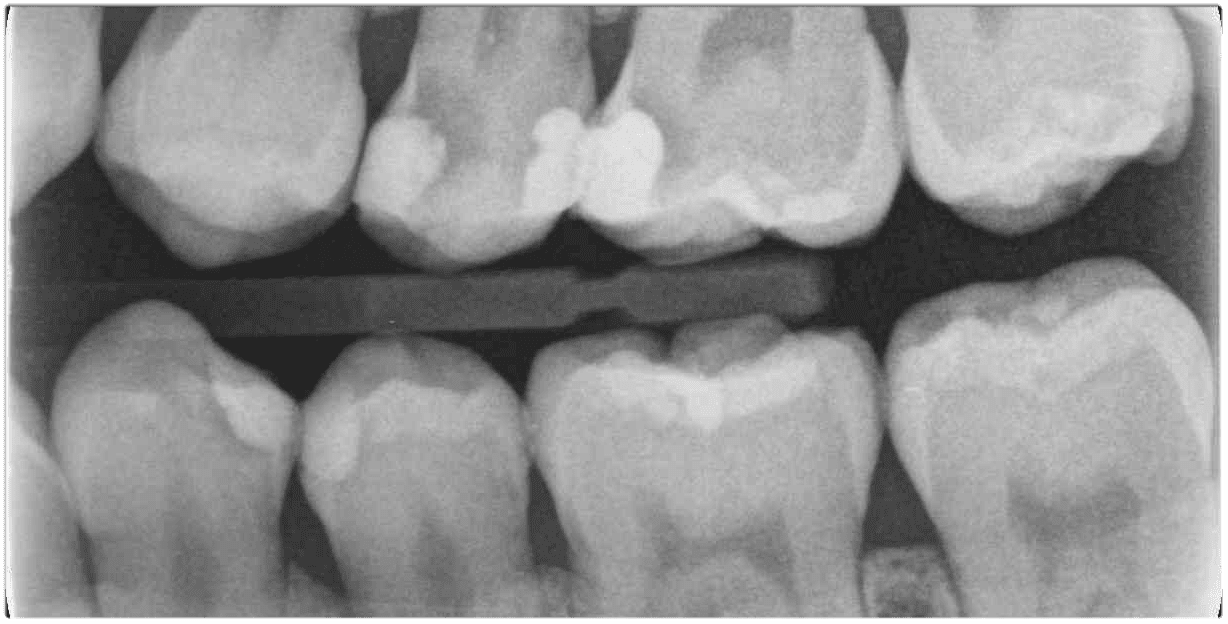

小朋友活髓治療

【活髓治療案例分享】應用在恆牙牙根未發育完全時牙髓壞死-黃小朋友

Apexogenesis和Apexification是什麼? 在發育中的牙齒患者中,不少見的是發現需要某種形式的根管治療, 例如Apexogenesis和Ape …